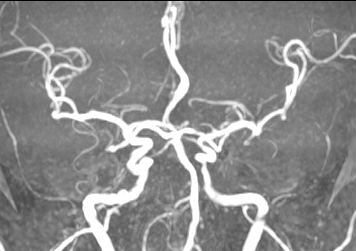

术后患者症状明显减轻,NIHSS评分2分。第二天复查MRA,血管保持通畅。